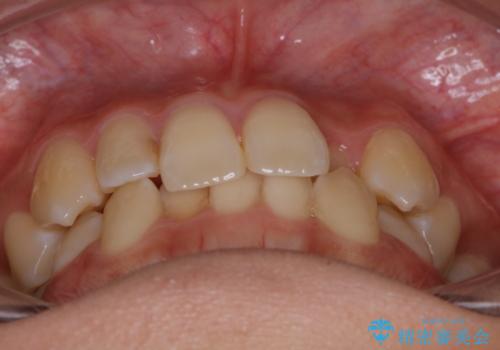

下顎前歯の先天欠損と上顎前歯のクロスバイト:インビザライン治療

- 上の前歯が1本後ろに入ってしまっていることが気になるとご相談にいらした方です。

クロスバイトしている歯が深く噛み込んでおり、この歯を外に出してくる際に強い咬合力が加わると歯が失活する恐れがあることを説明し、合わせて咬筋へのボトックス注入を行いました。